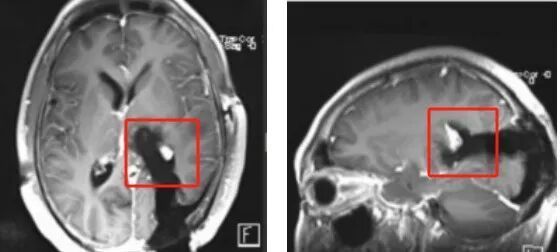

颅脑MR检查显示:左侧基底节区-丘脑-海马区域见一类圆形肿块,大小约45mm×42mm×40mm,初步考虑胶质母细胞瘤。胶质瘤是常见的原发性颅内恶性肿瘤,其中高级别胶质瘤侵袭性强、预后差,而发生于丘脑、基底节区等高危功能区的肿瘤,毗邻重要神经结构,此类手术需在最大限度切除肿瘤与最大限度保留功能之间实现精细平衡,一度被视为神经外科“手术禁区”,难度极大。

术前MR

术中增强MR